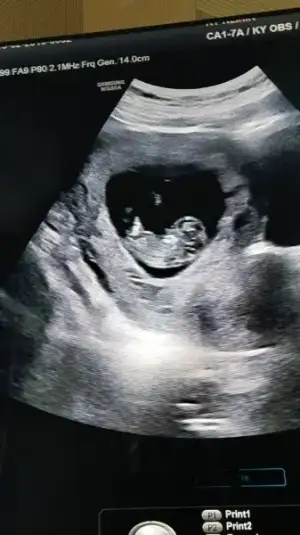

Söylemek istiyorum ama korkuyorum birazda kanama alanı konusu hep kafamı bulandırıyor. O olmasa belki söylerdim şimdi herkese. Bi sonraki kontrole gideyim hani kesin netleşsin öyle söylerim düşüncesi var şuan kafamda. Bugün 9+1 kontrole gittiğimde 11+3 olacak.